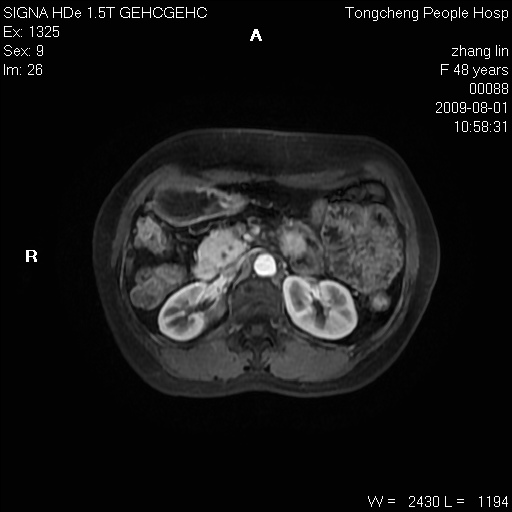

女,48岁。健康体检,彩超发现右肾占位性病变。平素健康。

临床诊断:右肾占位性病变,性质待定(囊肿?肿瘤?)。

上中腹部mr平扫+增强扫描,图像如下:

右肾上极见一类圆形病灶,t1wi呈等信号t2wi呈等高混杂信号,三期增强无强化,边界清---考虑囊肿出血。

同反相位均表现为等信号,病变无强化,考虑含蛋白的囊肿可能,弥散加权相或许有些帮助,

慢性胆囊炎